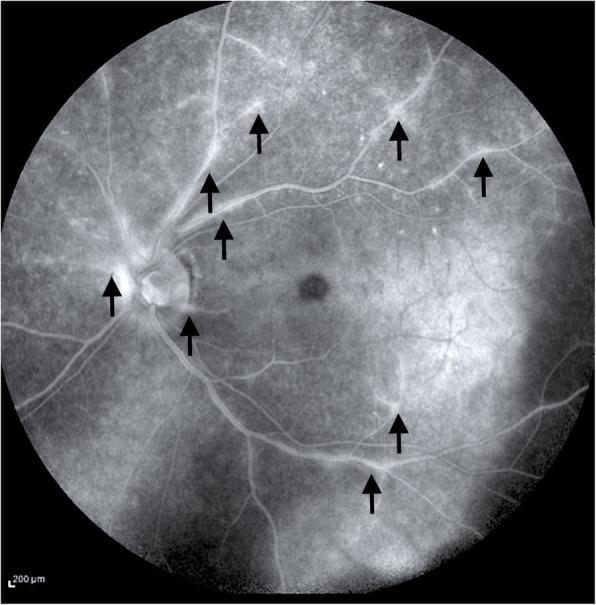

Acute syphilitic posterior placoid chorioretinitis: when the great mimicker cannot pretend any more; new insight of an old acquaintance.

Syphilis has started to attract the attention of researchers once again due to recent surges, with The World Health Organization (WHO) reporting around 12 million new cases per year. When left untreated, syphilis has a mortality rate of 8-58%, with a higher death rate in males. Eye manifestations occur both in secondary and tertiary stages of syphilis, although ocular involvement may occur at any stage of the disease. Syphilis has been always recognized as "the great mimicker" since it can have multiple clinical patterns of presentation. However, Acute Syphilitic Posterior Placoid Chorioretinitis (ASPPC) represents the typical pattern of the disease and can be easily distinguished. In addition, the advent of modern technologies and the progress made in multimodal imaging have provided more details on its identikit: the pattern of pre-retinal, retinal, retinochoroidal and optic nerve involvement can be identified before going through the laboratory work-up for a correct and appropriate investigation of the disease.

This review highlights the peculiar pattern of ASPPC, by reporting the diagnostic process made by all the imaging techniques used for a correct multimodal imaging assessment.